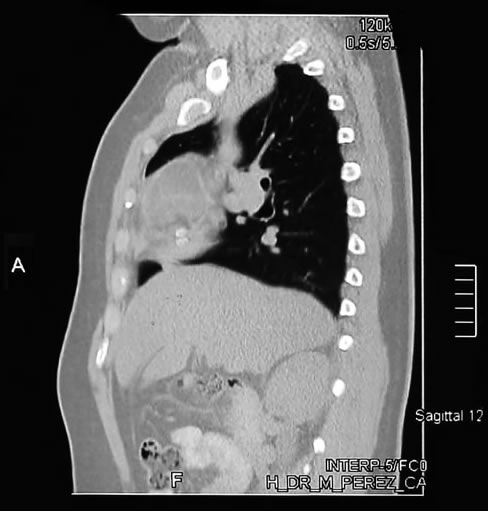

Tomografia Corte Sagital l2 hileo pulmonar derecho

Tomografia Corte Sagital l2 vena cava superior

Corte Sagital hileo pulmonar derecho

La misma imagen o corte superior demuestra que la lesión es encapsulada de contenido  heterogéneo y con  nódulo calcificado en su interior, demuestra su relación a los vasos del hileo pulmonar derecho posterior sin invadirlos.

Corte Sagital vena cava superior

El mismo corte sagital a nivel de la cava superior, demuestra la imagen en su mayor diámetro, de contenido solido, por su cápsula de aspecto brillante sin trabéculas ni tabiques en su interior.